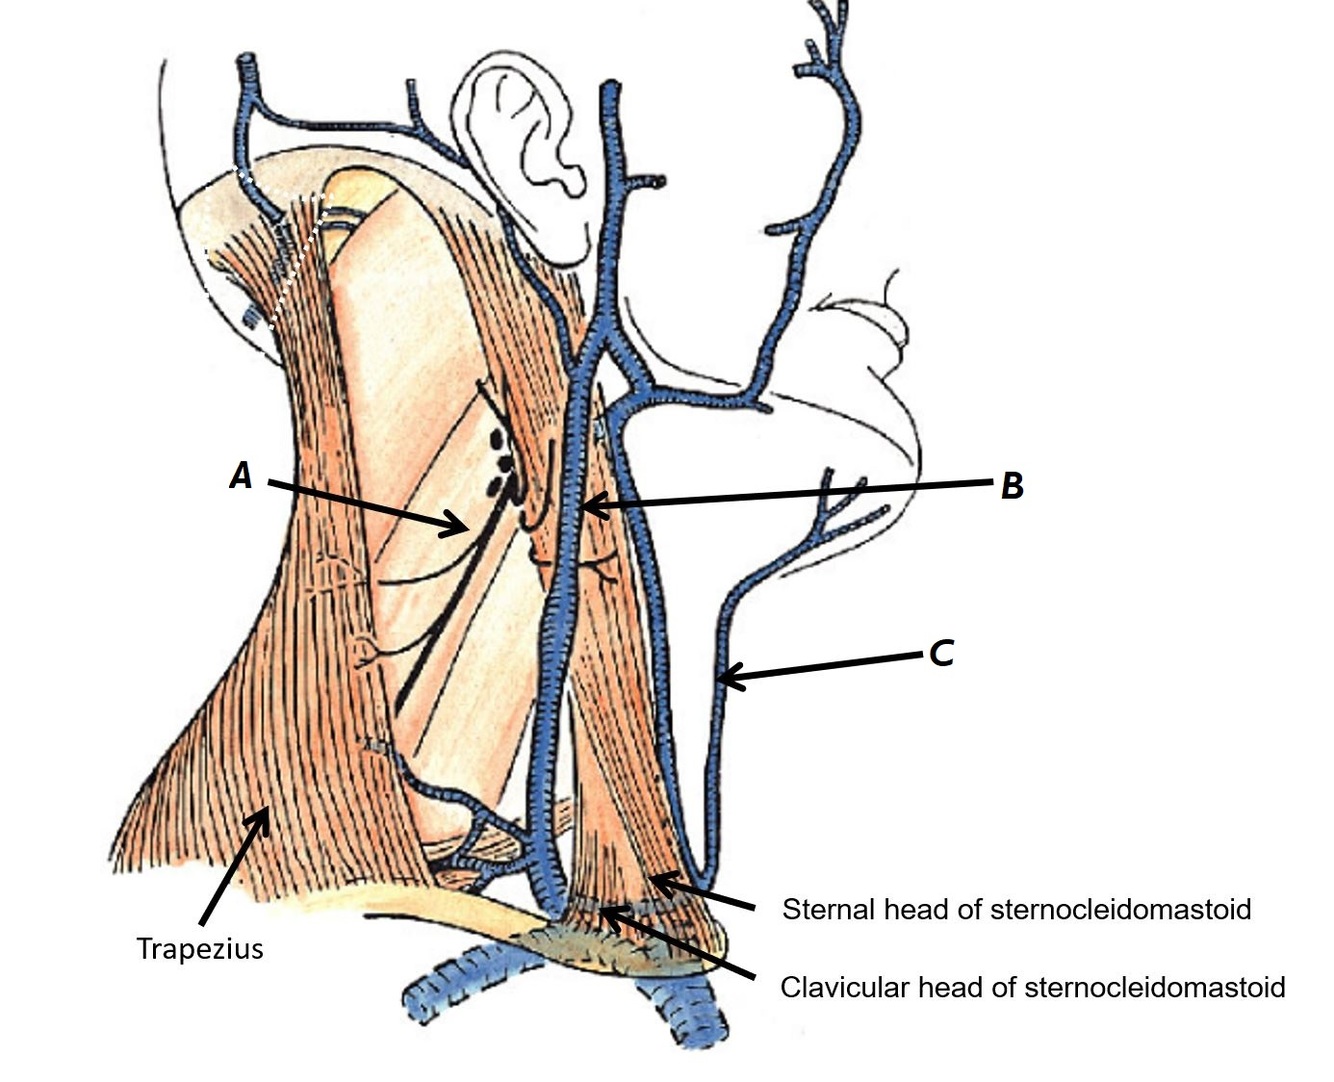

Name structures A, B and C

A - Spinal accessory nerve (CN XI)

B - External jugular vein

C - Anterior jugular vein